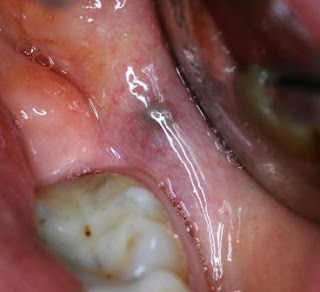

Paciente gênero feminino, melanoderma, por volta de 50 anos de idade, compareceu ao consultório com queixa de ter notado lesão negra em região retromolar, assintomática. Paciente receosa quanto a diagnóstico oncológico. Foi em dois dermatologistas e três cirurgiões-dentistas que deram o mesmo diagnóstico de hemangioma (técnica de vitropressão positiva). Foi feito, para segurança da paciente, acompanhamento por 8 anos até o momento e lesão permanece estável. A paciente continua em nosso serviço onde continuamos acompanhando lesão. Confira as fotos e um interessante esquema (retirado do livro Oral Medicine and Pathology at a Glance) para diagnóstico de lesões hiperpigmentadas.

| Foto inicial - 2005 |